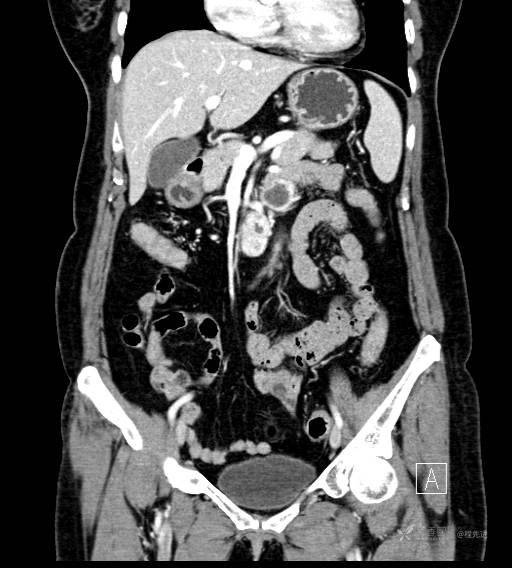

CT增强静脉期

CT增强冠状位重建